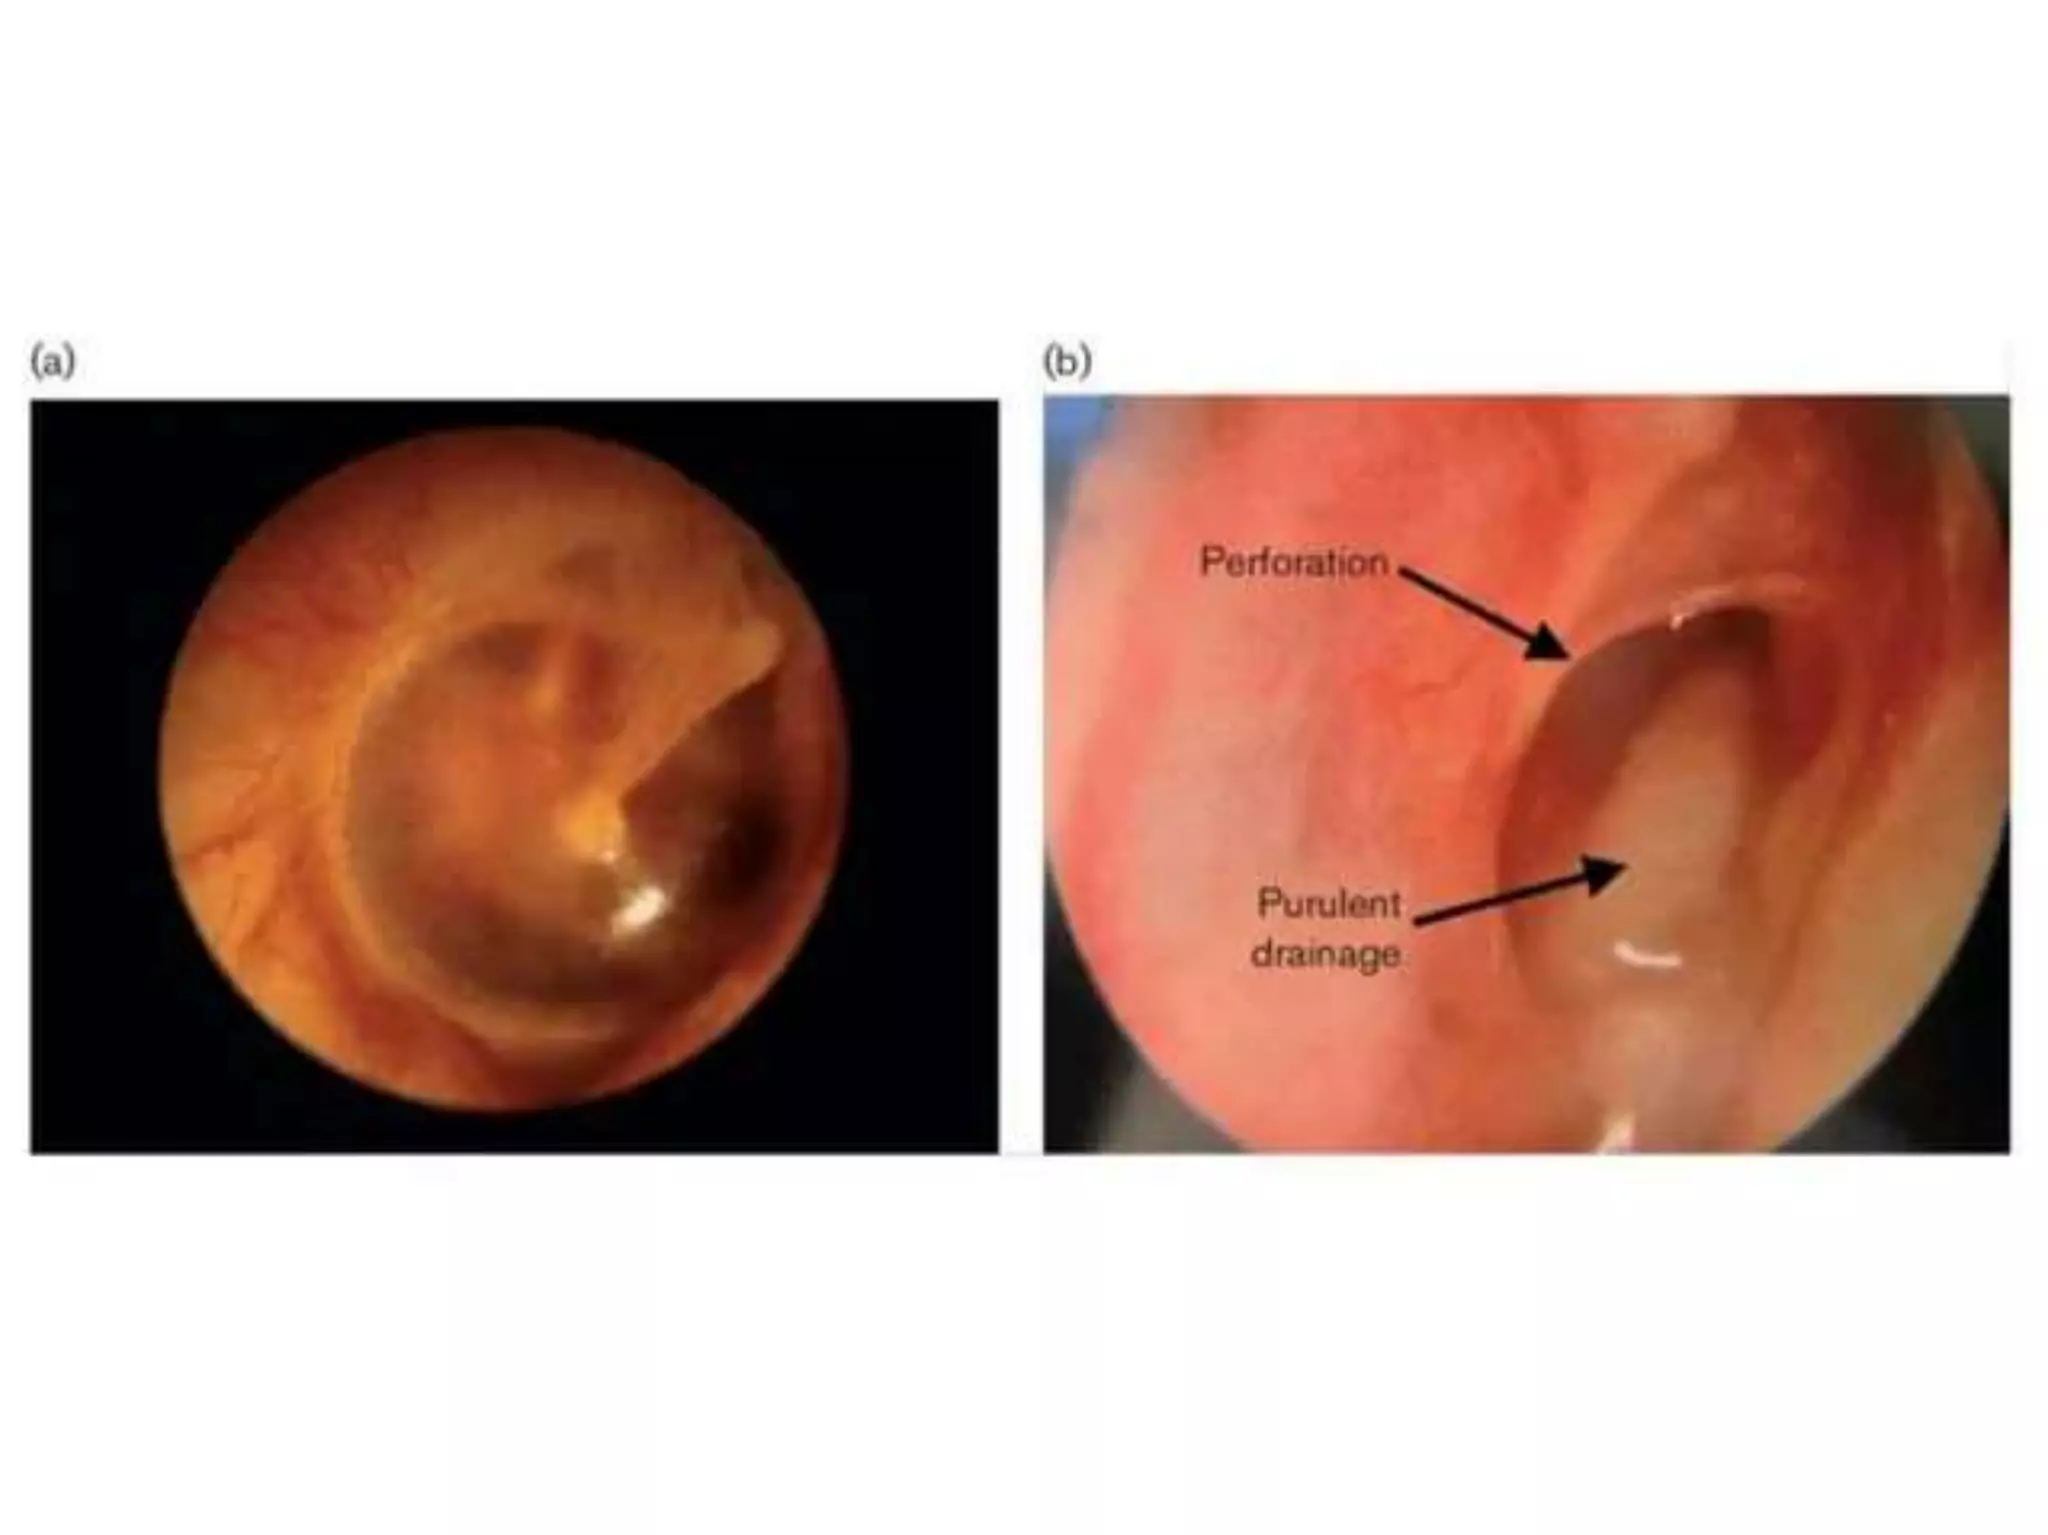

Chronic otitis media is a chronic inflammation of the middle ear and mastoid cavity that presents with recurrent ear discharge through a perforated eardrum. It has several subtypes depending on the state of the eardrum perforation and epithelium. It can be caused by prior acute otitis media, genetics, environment, eustachian tube issues, gastroesophageal reflux disease, craniofacial abnormalities, or immune deficiency.